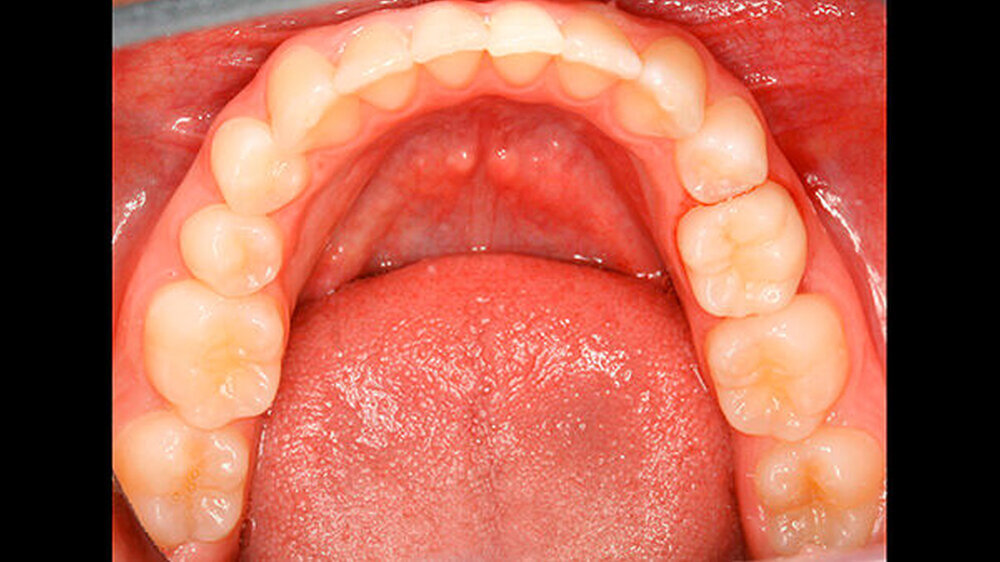

Die Patientin zeigte ein kariesfreies bleibendes Gebiss mit Nichtanlage des Zahns 35 und Persistenz des Zahns 75 auf (Abbildung 1). Sie wies im Frontzahnbereich sowie im rechten Seitenzahnbereich eine Klasse I auf, im linken Seitenzahnbereich aufgrund der Größe des Zahns 75 eine Klasse II. Zahn 75 befand sich in deutlicher Infraokklusion (Abbildung 2). Der Perkussionstest wies allerdings nicht eindeutig auf eine Ankylosierung hin.